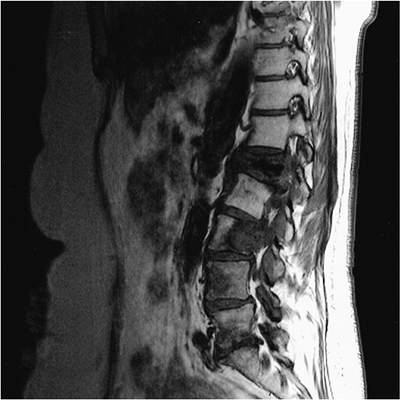

FIGURE 10-38

Sagittal T1-weighted image of the lumbar spine demonstrates a burst fracture of L1 with a large metastatic lesion in L3 extending into the posterior elements and a third lesion in L4. |